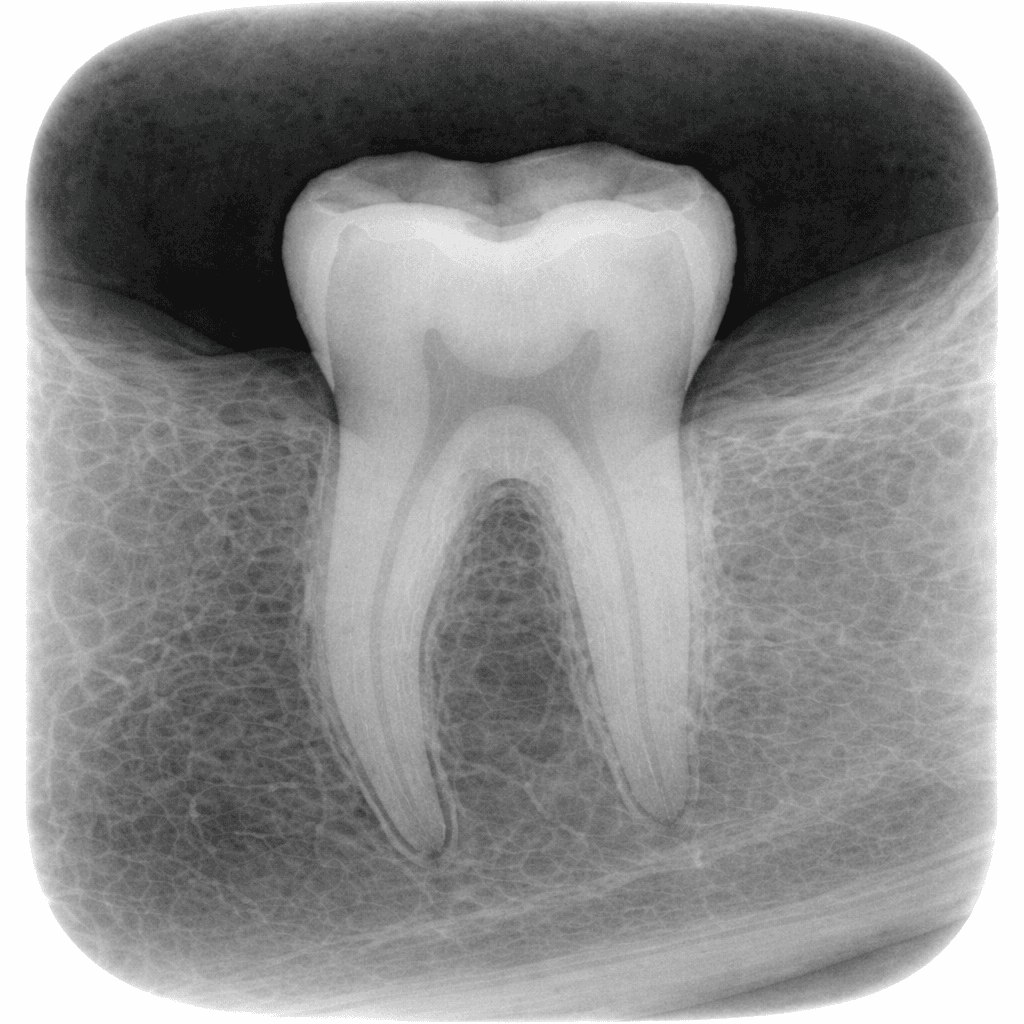

Periapical (P.A) X-Ray: Focused Detail Where It Matters

Periapical X-rays provide a close-up view of a single tooth, including its root and surrounding bone. This type of imaging is commonly used when a specific tooth is causing symptoms.

P.A X-rays are useful for:

Diagnosing tooth infections

Evaluating root canal conditions

Monitoring healing after treatment

They offer precise detail in a targeted area, making them efficient and informative.